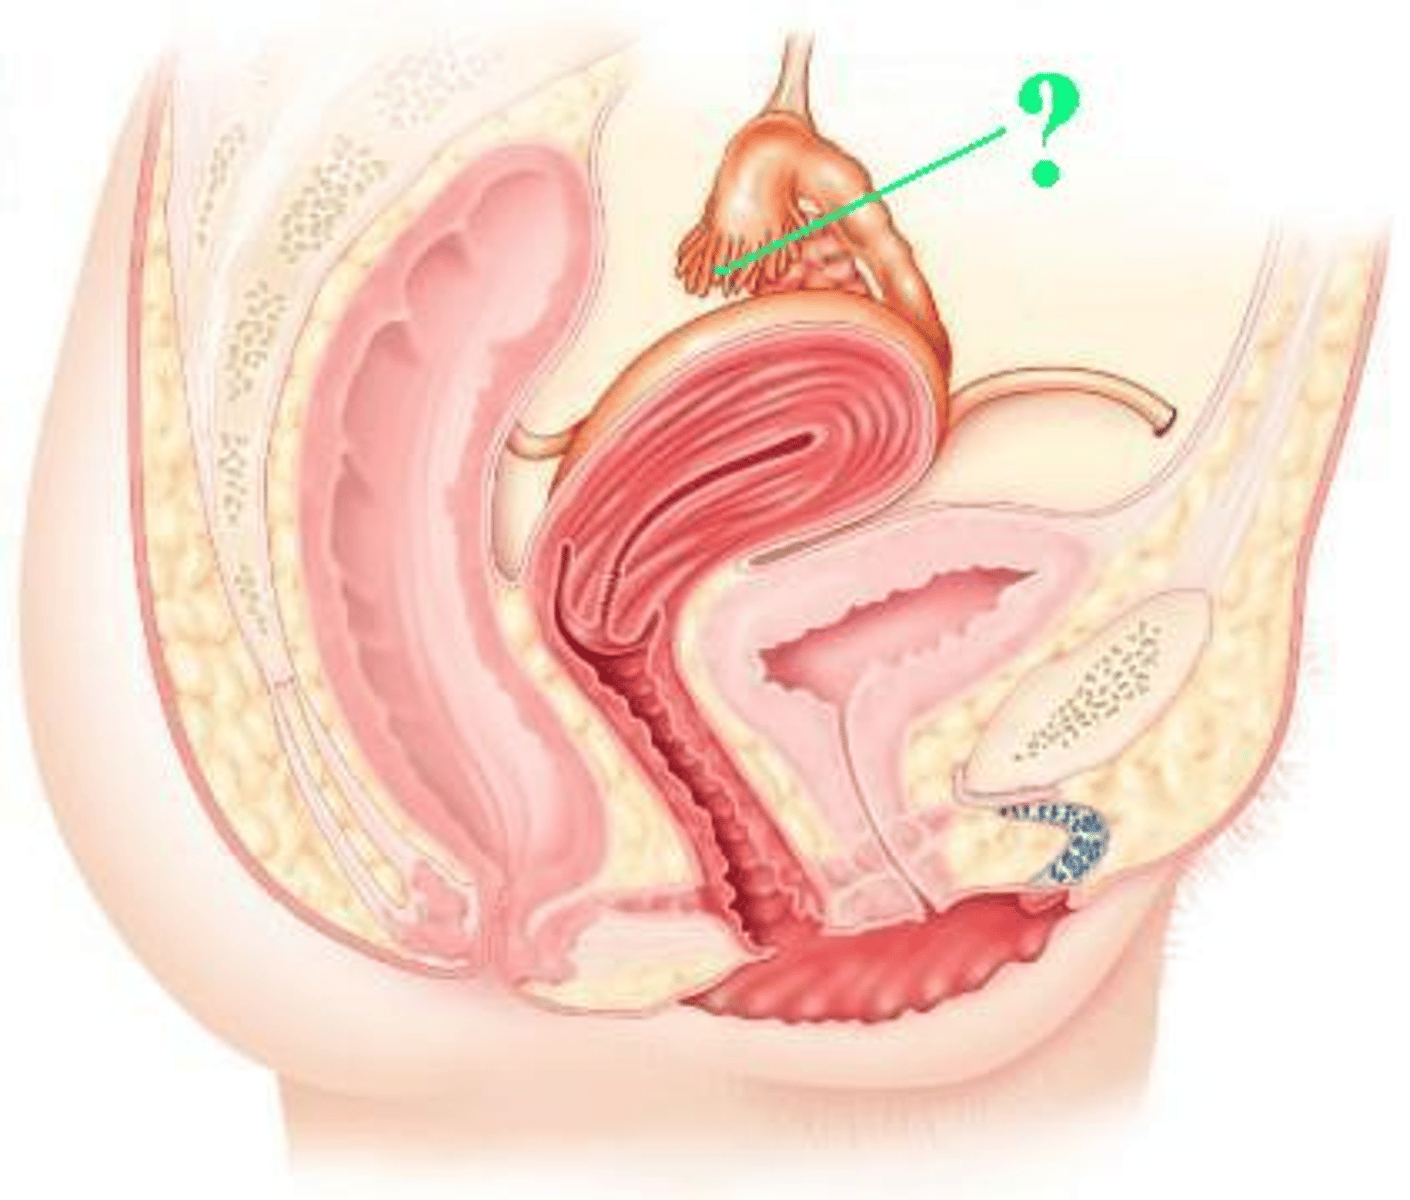

fimbriae

Identify the indicated structures.